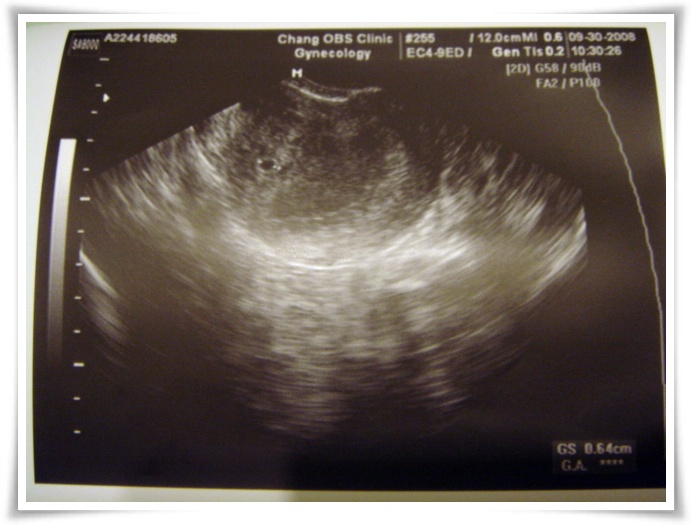

於是乎拖到今天才跟小bb第一次見面

這時的小bb 還只是個小胚胎 相信過一陣子 他就是個胎兒了

醫生說~他的形狀不漂亮